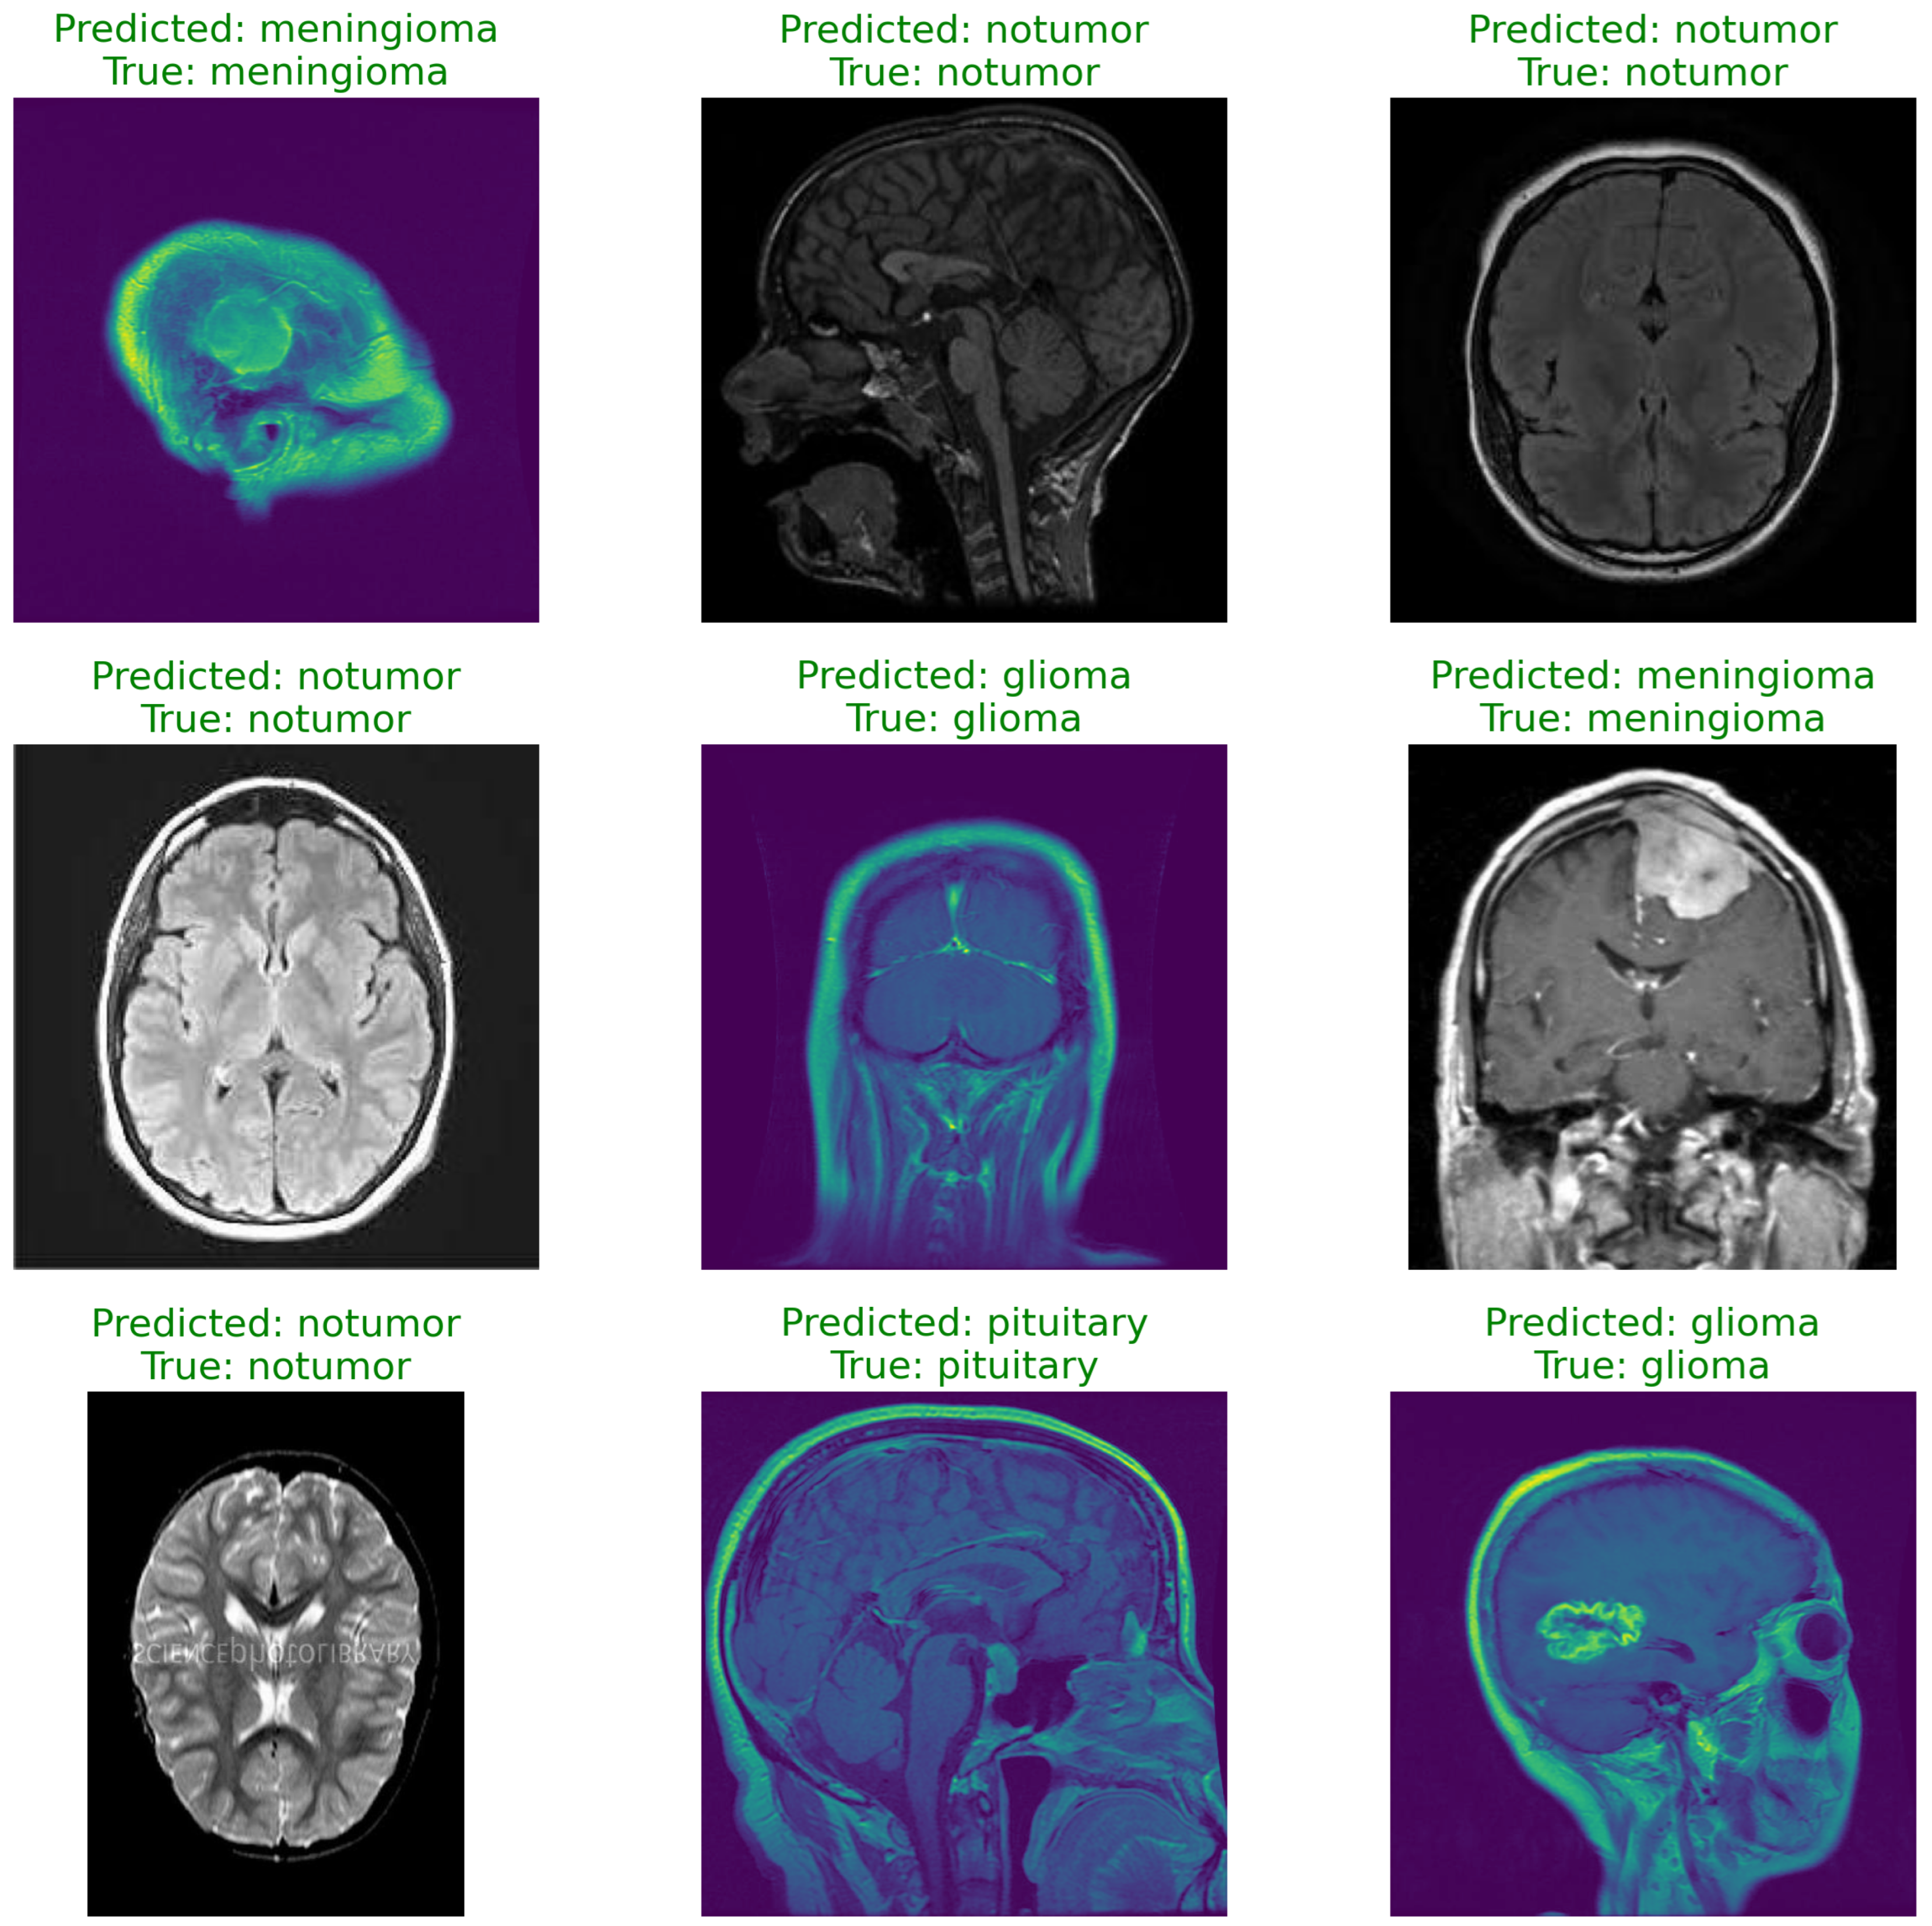

5. Results

5.1. Training and Validation

5.2. Performance Metrics

- Test Accuracy: 93.98%

- Confusion Matrix:

| Class | Precision | Recall | F1-Score |

| Glioma | 0.955 | 0.923 | 0.939 |

| Meningioma | 0.917 | 0.833 | 0.873 |

| No Tumor | 0.924 | 0.998 | 0.960 |

| Pituitary | 0.974 | 0.993 | 0.983 |

| Overall Accuracy | 0.941 |

6. Discussion